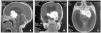

En un primer momento se cambia la lactancia artificial de inicio por un hidrolizado de proteínas de leche de vaca a la espera de los resultados de las pruebas complementarias sin que exista una mejoría clínica. Dentro de las exploraciones complementarias se realiza de forma escalonada: analítica sanguínea con parámetros nutricionales y estudio de inmunidad, serologías virales, analítica de orina, cribado de metabolopatías, ecografía abdominal, PRICK y RAST para proteínas de leche de vaca: todos ellos sin hallazgos de interés. Dentro del estudio sistemático se realiza una ecografía transfontanelar que evidencia tumoración quística hiperecoica de 45 mm en la región selar. La resonancia magnética craneal confirma una tumoración sólida supraselar situada a nivel del quiasma óptico que comprime hipotálamo y lóbulo frontal englobando los senos cavernosos (fig. 1). Ante la existencia de una tumoración diencefálica se solicita estudio de funcionalismo del eje hipotálamo-hipofisario que es normal. Tras analizar las posibilidades terapéuticas de forma multidisciplinar se decide realizar resección tumoral parcial a través de una craniectomía frontotemporal izquierda. Se remite a anatomía patológica la pieza quirúrgica siendo informada como astrocitoma fibrilar de grado bajo. Se inicia quimioterapia neoadyuvante con carboplatino y vincristina. A pesar del esfuerzo terapéutico la paciente presenta un empeoramiento progresivo. En los controles por neuroimagen se detecta una progresión tumoral y la aparición de metástasis leptomeníngeas. Finalmente fallece a los 3 meses del diagnóstico.

Figura 1.Tumor sólido supraselar de 4,2 × 3,7 × 3,2 cm, a nivel del quiasma óptico, con pequeño componente quístico que presenta captación intensa de contraste.